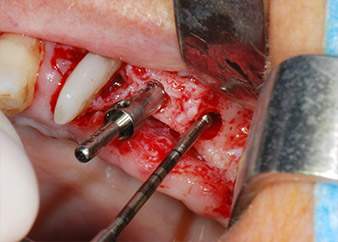

En el siguiente paso, los lechos del implante se prepararon en las posiciones 25 y 26 con instrumentos rotatorios, utilizando un contra-ángulo con un coeficiente de transmisión de 20:1 (WS-75 L, W&H), junto con el nuevo potente motor de implantes Implantmed de W&H (figuras 8 y 19).

A continuación, los implantes (Restore, Keystone Dental, 3,75 mm de diámetro, 8,0 mm de longitud) se colocaron con el motor de implantes (figuras 11 y 12).

listos para los tornillos de cubierta

Fig. 12: Los dos implantes están colocados y listos para los tornillos de cubierta.